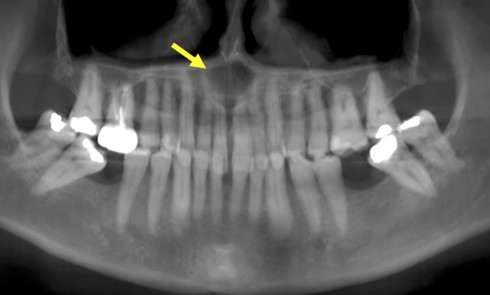

Langue géographique (fig. 6)

Elle correspond à une variation clinique de l’exfoliation linguale physiologique. Sa prévalence est comprise entre 1 % et 2,5 %. Il s’agit d’une variante buccale du psoriasis. La langue géographique se présente dans sa forme la plus commune par un aspect circiné blanc jaunâtre bordant une zone érythémateuse à côté d’une muqueuse d’aspect normal. Elle est caractérisée par un œdème important au niveau des bordures jaunâtres, faisant éclater…